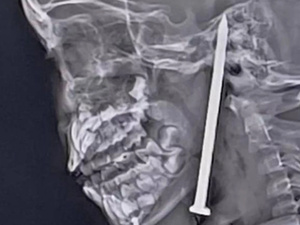

أظهرت الفحوص بالأشعة المقطعية مدى خطورة الإصابة، مما استدعى تدخلاً جراحياً عاجلاً. ورغم التحديات الكبيرة، نجح الأطباء في استخراج المسمار دون التسبب بأي ضرر عصبي مباشر. بعد الجراحة، نُقلت الطفلة إلى قسم العناية المركزة حيث وُضعت على جهاز تنفس صناعي وظلت تحت مراقبة دقيقة لمدة 10 أيام للوقاية من التورم والالتهابات أو أي مضاعفات عصبية.

في 29 مايو، أُعلن عن نقل الطفلة إلى غرفة عادية بعدما استعادت وعيها بالكامل واستجابت بشكل إيجابي للعلاج، دون تسجيل أي عجز عصبي. وأكد الأطباء أن الطفلة تتماثل للشفاء التام ومن المتوقع أن تعيش حياة طبيعية، واصفين نجاتها بـ"المعجزة الطبية".